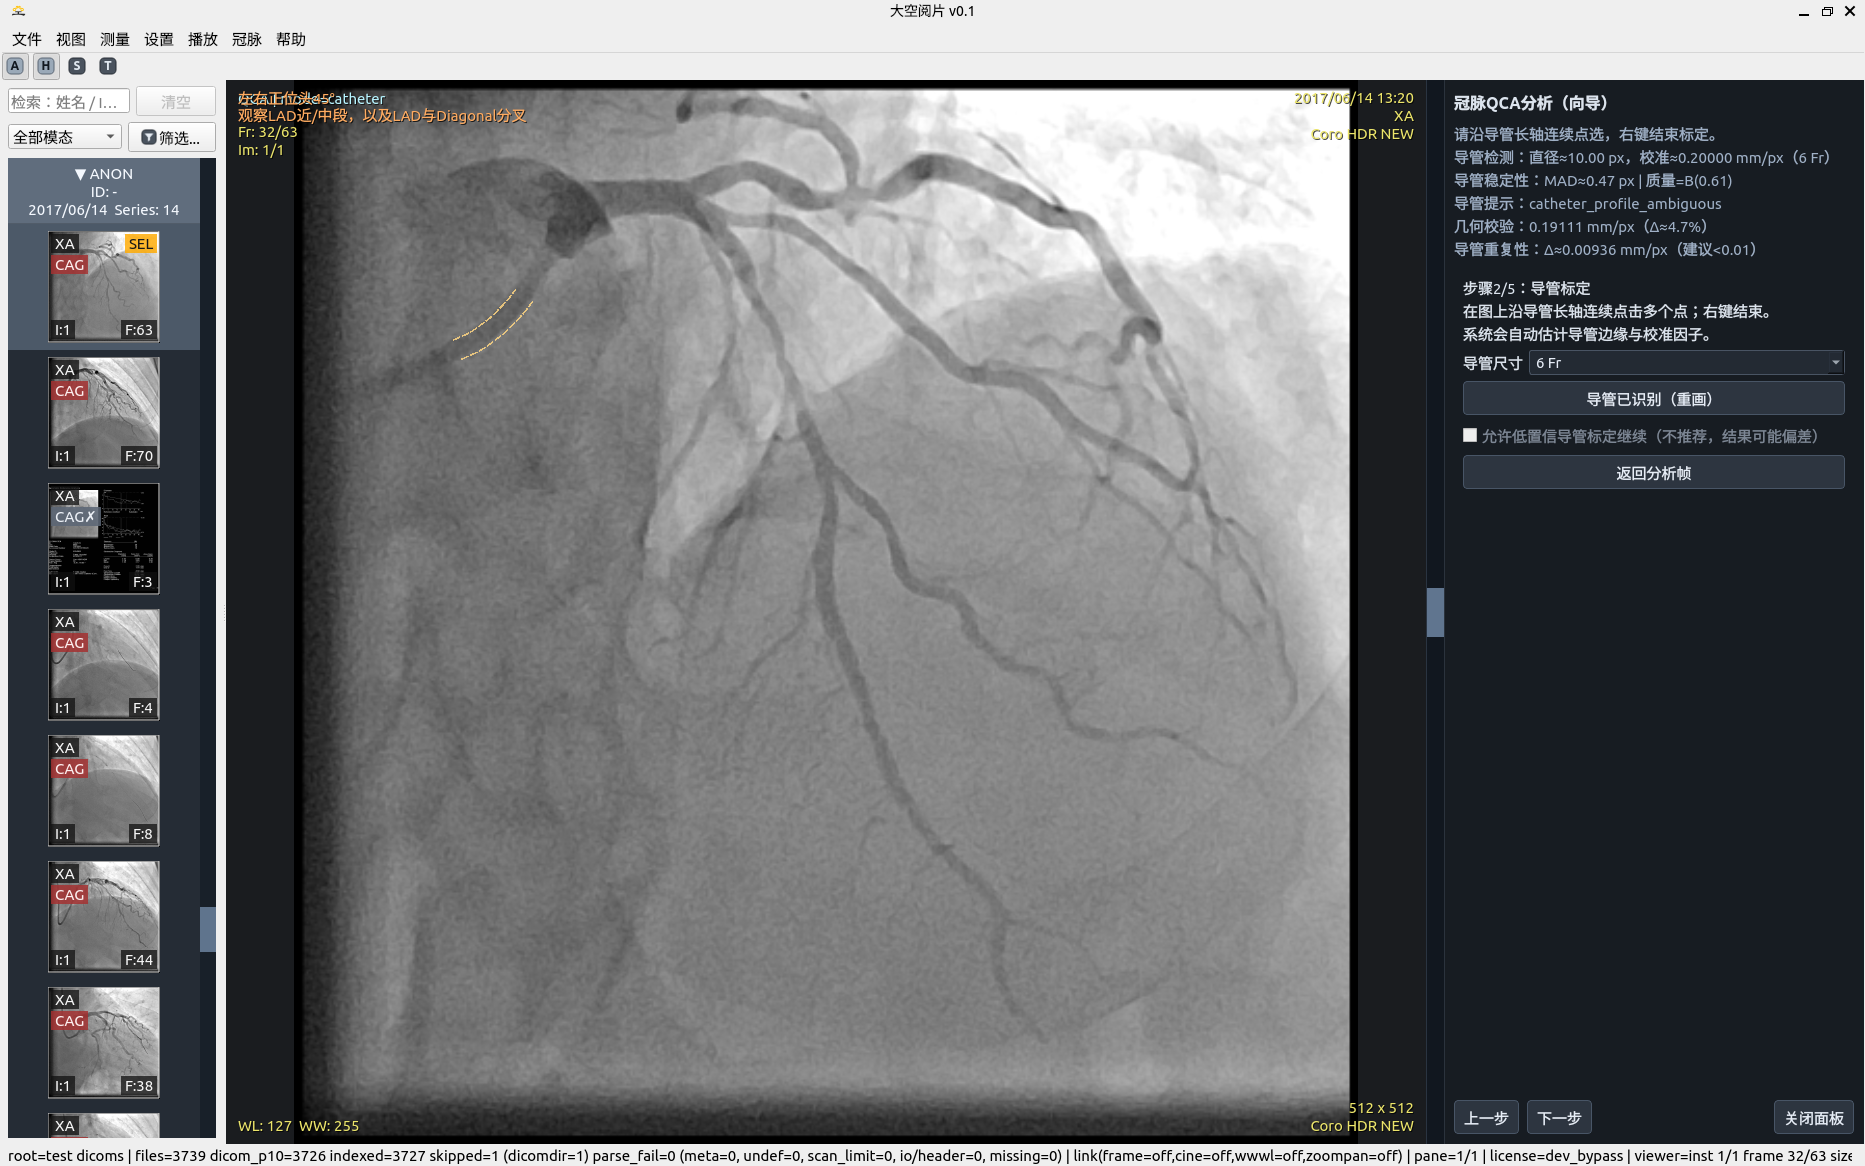

5. 冠脉 QCA 分析

半自动流程强调“可解释 + 可修正 + 可重算”,而非一次性黑盒输出。

• 导管标定:拉直空间剖面 + 左右联合动态规划(DP)+ 亚像素修正。

• 边缘检测:极性自适应 + 有符号边缘特征 + 联合状态 DP + 多峰歧义度。

• 稳健性:MAD 统计、质量等级、结构化告警与恢复建议。

• 几何交叉校验:SID/SOD/ERMF/像素间距参与比例复核。

移动端请按步骤顺序阅读:步骤 1 → 步骤 7。

QCA 分析步骤 2

导管校准